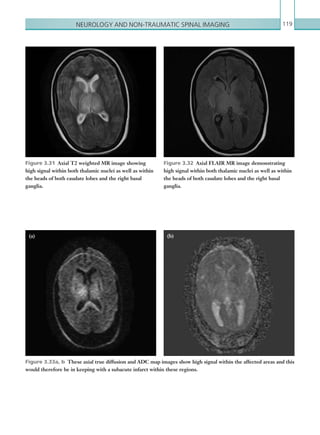

Date

Reporting radiologist

CT CHEST: Pneumothorax/haemothorax/pneumomediastinum/thoracic aorta injury

Rib #...........................................................................Thoracic spine #..................................................................................